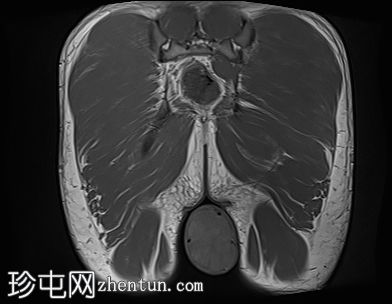

冠状位

T1加权像

阴囊内睾丸增大,T1加权像上可见分叶状软组织病变,呈中高信号,T2加权像上呈低信号。

轻度双侧鞘膜积液。

本病例表现为双侧睾丸肿胀,影像学特征符合睾丸肾上腺残余肿瘤的典型表现,即T1加权像上呈双侧中高信号,T2加权像上呈低信号。